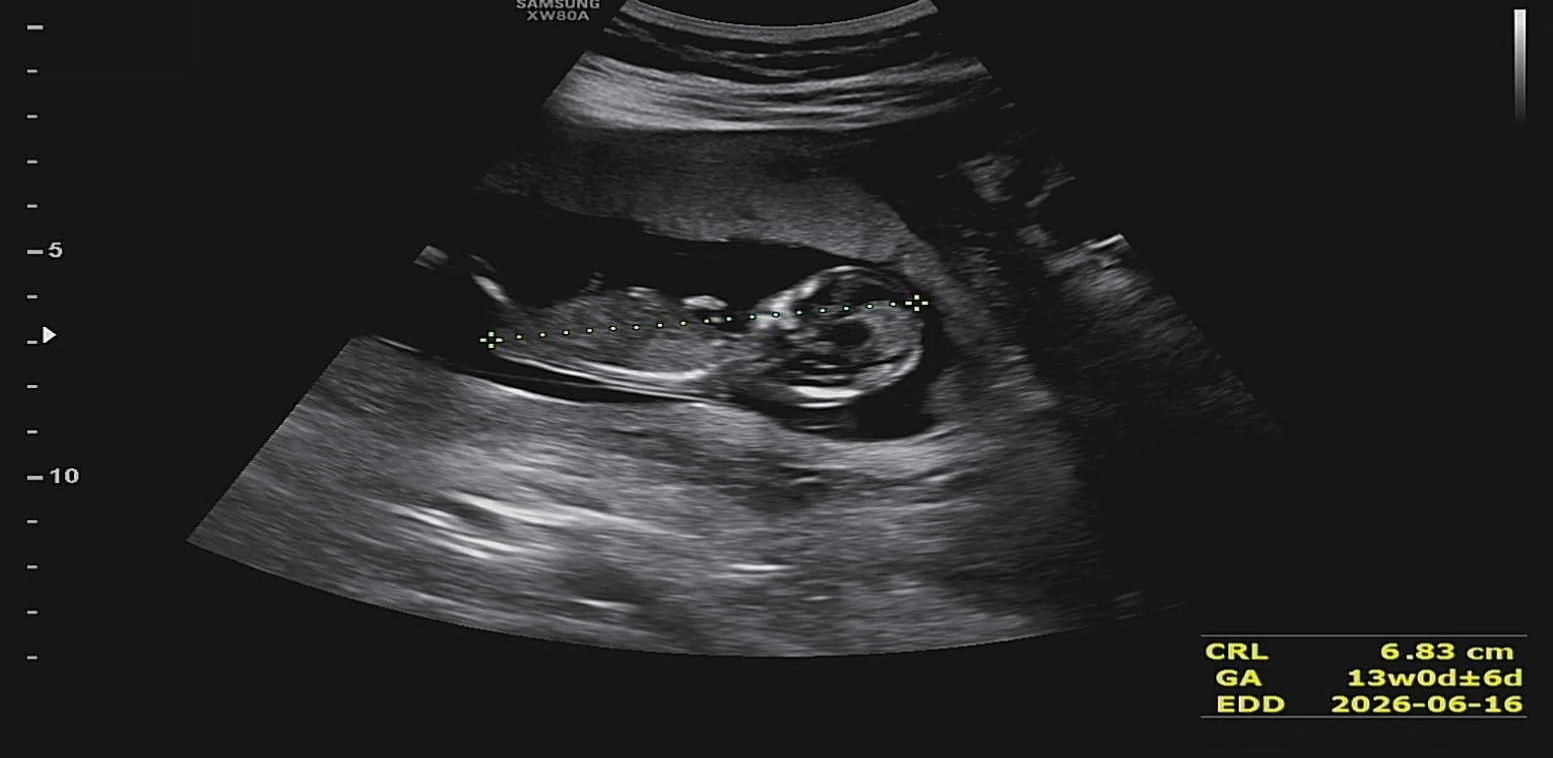

2026년 6월 베동

아기가 다리를 쭉 펴고 있어요 각도법 고수 선생님들 도와주세요